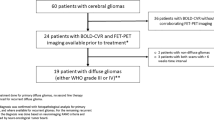

No significant association existed between AI and the number of voxels evaluated for any of the parameter–tissue combinations. Summary AI data for each measured parameter–tissue versus time since surgery are shown in Fig. 2.

Asymmetry index for cerebral blood flow (CBF), cerebral blood volume (CBV), and fractional anisotropy (FA) in cerebellar grey matter (cGM) and cerebellar white matter (cWM). The points represent the mean and standard error of the asymmetry index across patients at each nominal protocol time point. The regression lines represent the fixed effects from the full mixed-effects model. The asterisk (*) indicates a significant, non-zero intercept for CBF and CBV in the gray matter, and solid lines indicate significant slopes for CBV in gray matter and FA in white matter

Hemodynamic changes were more robust in cGM than in cWM. During the first postoperative study, 7 patients had decreased blood perfusion within cGM contralateral to supratentorial lesion, and the asymmetry was statistically significant (intercept of the fixed effects regression) for both CBV (p = 0.008) and CBF (p < 0.01). The asymmetry was in the range of 3–15 % (median 6 %) for CBV and 2–6 % (median 4 %) for CBF. Asymmetry of CBV trended significantly toward recovery (p < 0.02), reaching symmetry after 2 years. In contrast, CBF remained asymmetric for the duration of the study. The regression of CBV and CBF in cWM was not significant. The pattern of hemodynamic changes in cWM suggests a paradoxical increase after surgery and a large decrease at first follow-up, perhaps representing a delayed response in the white matter compared to the more metabolically active gray matter.

DTI changes were more pronounced in cWM than in cGM. The FA in contralateral cWM steadily declined (p = 0.003), without evidence of recovery during the follow-up period. FA in cGM followed a similar trend; however, the slope was not statistically significant. The decline in cWM FA contralateral to the supratentorial lesion was associated with an increase in radial diffusivity (p = 0.04), with no systematic change in the axial diffusivity (Fig. 3).